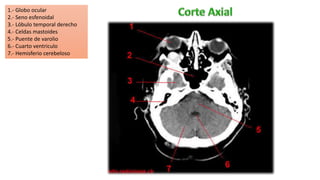

1.- Globo ocular

2.- Seno esfenoidal

3.- Lóbulo temporal derecho

4.- Celdas mastoides

5.- Puente de varolio

6.- Cuarto ventriculo

7.- Hemisferio cerebeloso